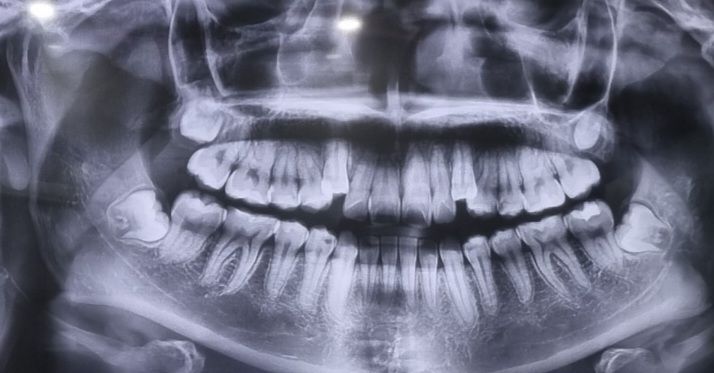

상하좌우 사랑니 한번 봐주실 분..?

아직 아프거나 나진 않았는데 매복인가요?

나중에 큰병원 가게 생겼나요..?

저 오른쪽 위에 사랑니는 왜 저렇게 생겼을까요...

사랑니가 매복되어 있는 상태이며 일반 치과보다는 대학병원이나 사랑니치과를 가시면 됩니다.

4개 사랑니 모두 매복상태 인거 같습니다. 크게 어렵진 않지만, 일반치과에서 발치가 안되면 대학병원이나 사랑니 전문 병원으로 가시는게 좋습니다.

넷다 매복이고 사진상 오른쪽 위(실제로는 왼쪽 위) 사랑니의 경우 회전되어 있으면 저렇게 작게 보일수도 있고 실제로 크기가 작을수도 있습니다 사랑니는 모양변이가 다양합니다

아직 사랑니가 다 자라지 않았습니다 보통 매복사랑니는 20대 초반에 보고 발치가 필요할지 결정하게 됩니다